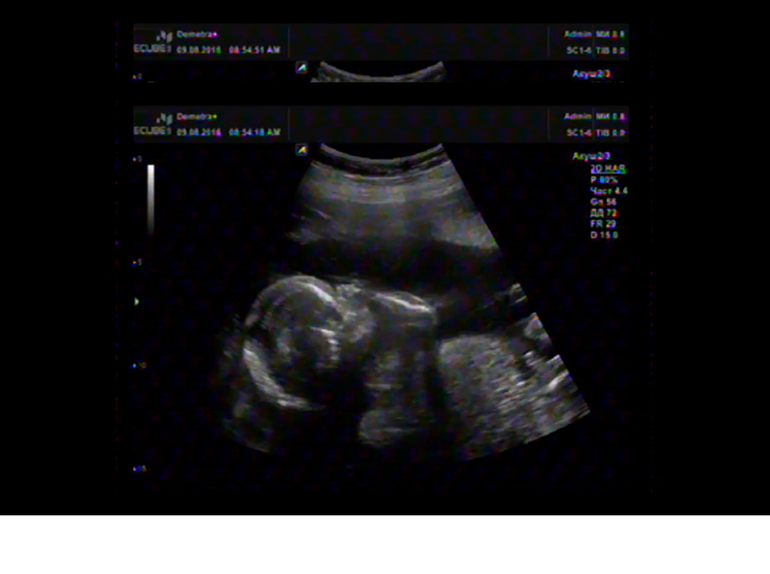

Я вижу пуповину, немного не удачный ракурс, чтобы разглядеть, немного правее бы.

Фото не в том ракурсе, чтобы видеть писюн, тем более размером с палец руки. То, что многие принимают за писюн, вполне может быть частью живота.

Я тоже не специалист, но писюн вижу! Так крууууто! А сколько вам недель ?